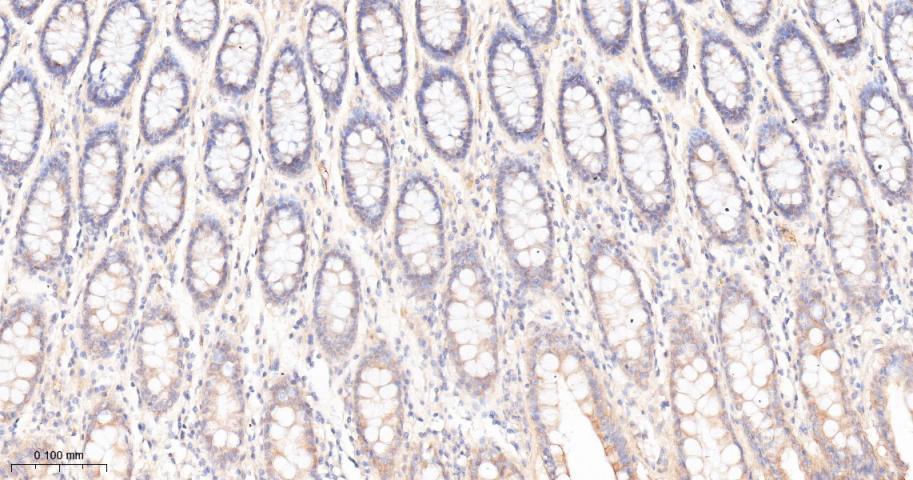

Paraformaldehyde-fixed, paraffin embedded Human Colon; Antigen retrieval by boiling in sodium citrate buffer (pH6.0) for 15 min; Antibody incubation with PON1 Monoclonal Antibody, Unconjugated(bsm-62941R) at 1:200 overnight at 4°C, followed by conjugation to the bs-0295G-HRP and DAB (C-0010) staining.

Paraformaldehyde-fixed, paraffin embedded Rat Colon; Antigen retrieval by boiling in sodium citrate buffer (pH6.0) for 15 min; Antibody incubation with PON1 Monoclonal Antibody, Unconjugated(bsm-62941R) at 1:200 overnight at 4°C, followed by conjugation to the bs-0295G-HRP and DAB (C-0010) staining.

Paraformaldehyde-fixed, paraffin embedded Mouse Colon; Antigen retrieval by boiling in sodium citrate buffer (pH6.0) for 15 min; Antibody incubation with PON1 Monoclonal Antibody, Unconjugated(bsm-62941R) at 1:200 overnight at 4°C, followed by conjugation to the bs-0295G-HRP and DAB (C-0010) staining.